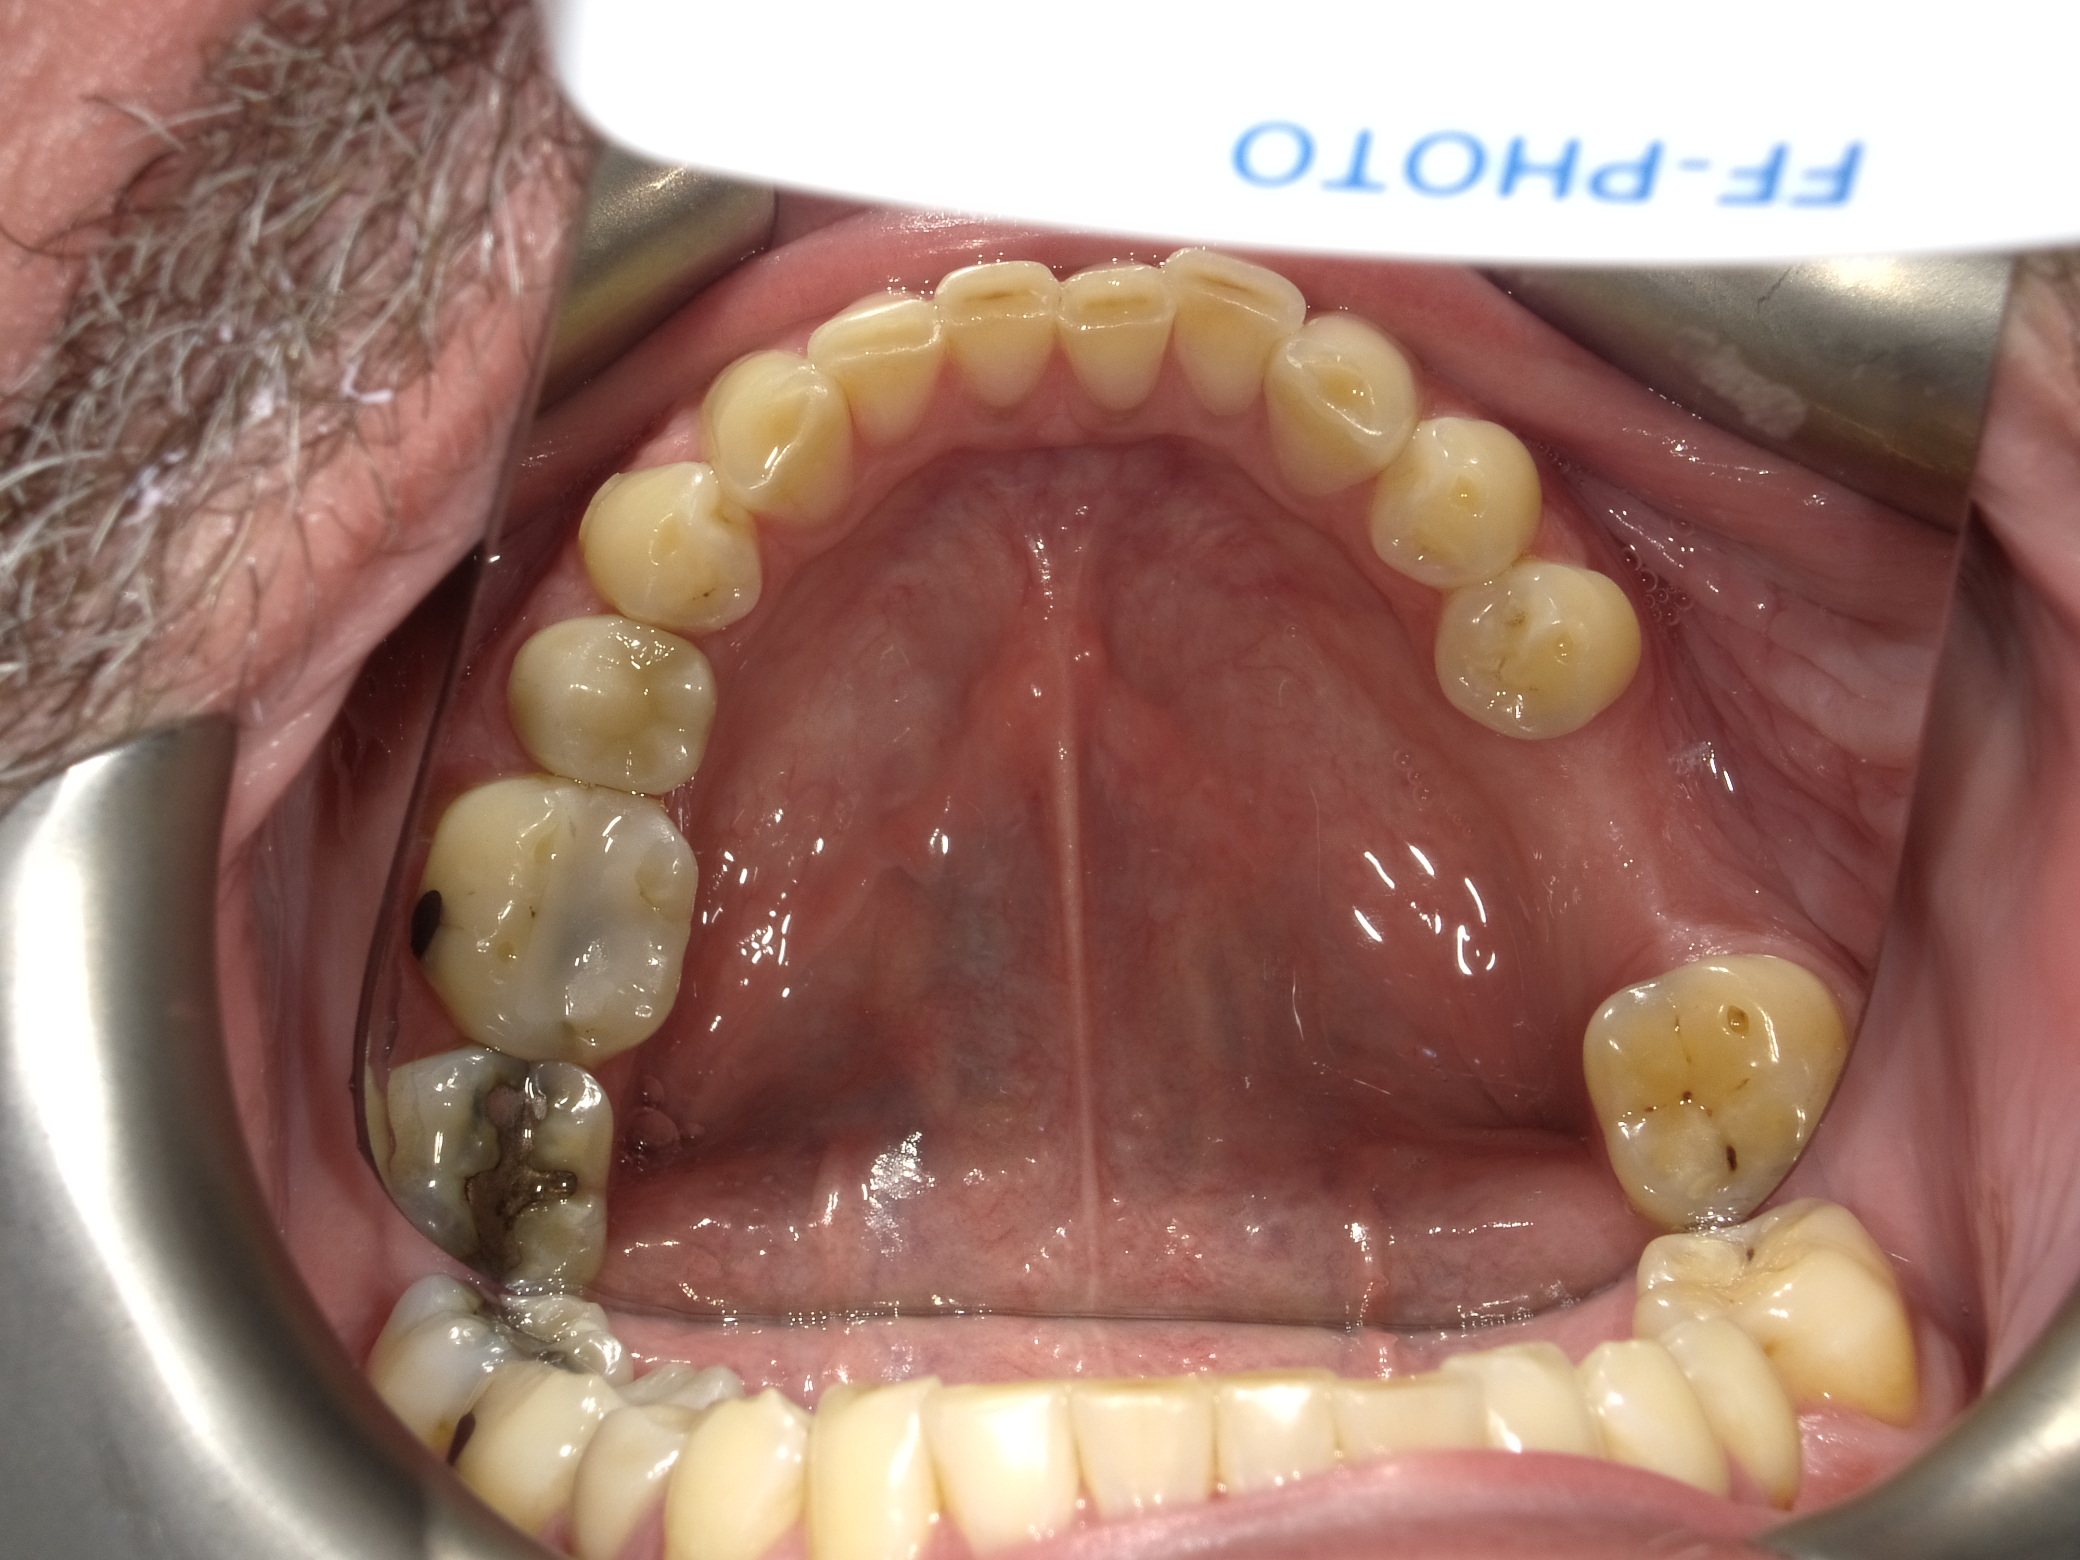

Fig 4. Extra-oral photography. All dental practices should provide the patient with the following four extra-oral photographs: the close-up smile (Fig 1), the retracted smile (Fig 2), the upper arch (Fig 3), and the lower arch (Fig 4).

Figure 4

Extra-oral photography. Extra-oral photography is essential for giving patients a full picture of their smile and oral health status. This has been a challenge for most dentists over the past two decades because many cameras that have the capability of taking high-quality, fully focused images of the dental arch have been difficult to use and program and awkward to sterilize. Other dentists have limited their use of such cameras to the occasional cosmetic case. However, extra-oral photography should be provided for every patient. The use of such photography and the type of photographs taken can vary from office to office, depending on the patient flow and the availability and training of personnel at that particular office. Regardless of these variations, however, all dental practices should take the following four extra-oral photos: the close-up smile, the retracted smile, the upper arch, and the lower arch (Figure 1 through Figure 4).

Intra-oral photography. Many dental conditions involve the margins between the natural tooth and the old restoration, which can be difficult to adequately capture with either traditional radi- ography or extra-oral photography. Every operatory should therefore be equipped with a high-quality intra-oral camera; sharing such photographs with the patient during the consultation is quite helpful in explaining the need for longer-term restorations. A well-trained dental hygienist or assistant can quickly  and seamlessly integrate several intraoral photographs during the new patient interview (Figure 5 and Figure 6), discussed below.